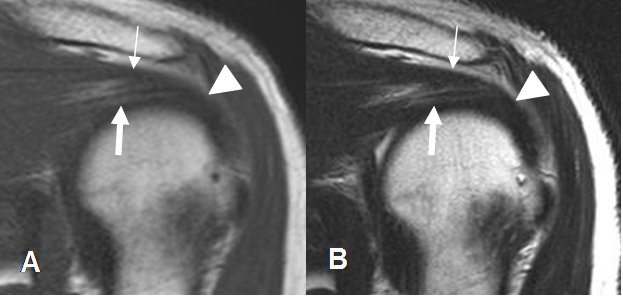

Los tendones del supraespinoso e infraespinoso se fusionan 15 mm antes de su inserción, en la parte mas superior de la tuberosidad mayor. (3). El redondo menor se inserta en la región infero-posterior de la tuberosidad mayor y el subescapular en la tuberosidad menor. (3). (Fig 1 A y B).

Fig 1B. Manguito rotador.

A: RM coronal en T1 y B: RM coronal en T2. Fusión de los tendones supraespinoso (Flecha delgada) e infraespinoso (Flecha gruesa), antes de su inserción conjunta en la tuberosidad mayor. (Punta de flecha).